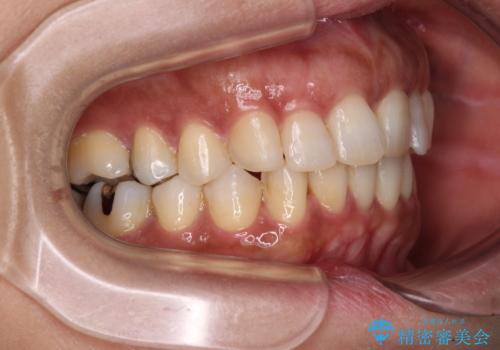

- 上下前歯のデコボコ改善をインビザラインにて行いたいとのことで来院された患者様です。

インビザラインをご希望のことで、IPR(歯と歯の間を削る)などによりスペースを獲得して、排列していくこととしました。

骨格的に上下顎が左右にずれていたため、正中位置は現状を維持したまま歯列不正を解消していくことになります。

なかなか装着時間が守れず、後戻りを繰り返しながら治療を進めたため、インビザライン治療期間期限ギリギリの5年弱の期間を要しました。